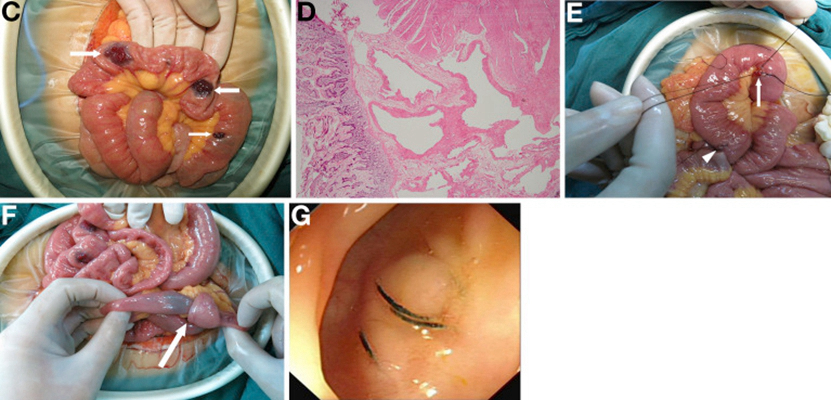

結腸癌症狀 (37)

結腸癌症狀 (38)

結腸癌症狀 (39)

結腸癌症狀 (4)

結腸癌症狀 (40)